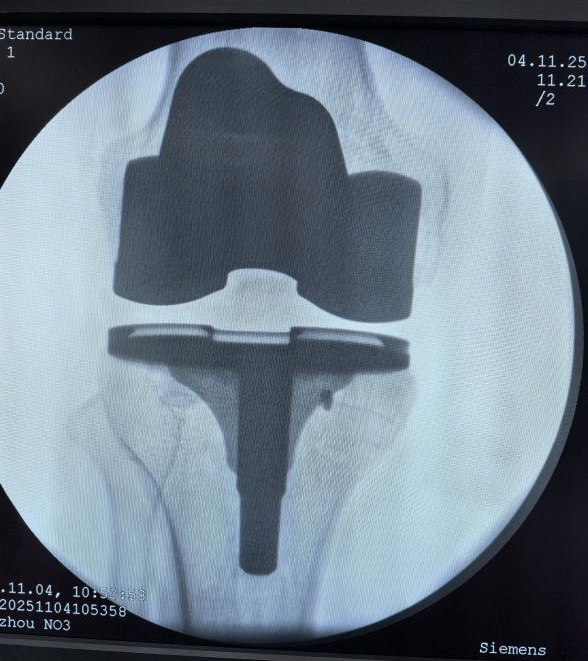

11月4日上午,我院骨科团队成功完成首例骨科机器人辅助全膝关节置换手术,标志着我院骨科诊疗技术正式迈入智能化、精准化、微创化的新阶段,推动了郴州地区骨科手术由传统手术向智能化发展迈出了一大步。

骨科主任胡伟文教授介绍,与传统手术相比,机器人辅助手术如同为医生装上了“透视眼”和“稳定手”。本次手术中,胡伟文主任团队借助先进的骨科手术机器人系统,术中在患者股骨和胫骨上安装追踪阵列及检查点针来精准导航,并采集患者的术前力线和膝关节运动范围等资料,通过机器人的精准计算规划出关节假体的尺寸、安装位置和关节间隙等,医生确认后由机器人的机械臂按照预设的最优方案稳定运行,精准抵达预定位置,有效规避了重要的神经和血管,将手术创伤降至最低。整个手术流程流畅,术中出血少,大大提升了手术质量和安全性。

机器人辅助手术在精准度方面实现了质的飞跃,其截骨精度可达0.1毫米以内,角度误差控制在0.1°以内,综合定位误差仅为0.87毫米,使假体与骨骼贴合度更好,力线恢复更准确,有望延长假体使用寿命。此外,系统基于术中精准的数据采集,智能生成手术方案并允许医生调整个性化手术方案,真正实现“一人一策”,使手术方案与患者个人解剖结构高度匹配。

据了解,该手术由骨科主任胡伟文教授团队联合我院麻醉科手术室等相关科室协作完成。患者为一名膝关节严重退变的老人,术后次日即可下床活动,目前恢复良好。手术的成功开展,不仅体现了医院骨科在微创和智能化技术领域的深厚积累,也展现了多学科协作(MDT)模式下医疗技术的综合创新实力。